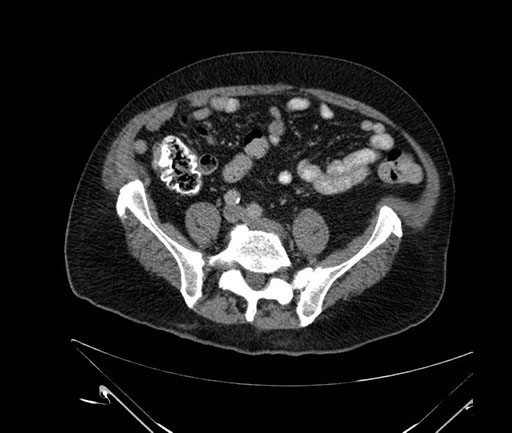

Imaging Analysis

Look through the patient's CT scan to identify any areas of concern for the necessary procedure.

Based on your CT findings, which issue(s) would give reason for "planned slowing down moment(s)" in this case?

Considering a standard Whipple procedure, what step(s) of the operation would you do differently in this case?